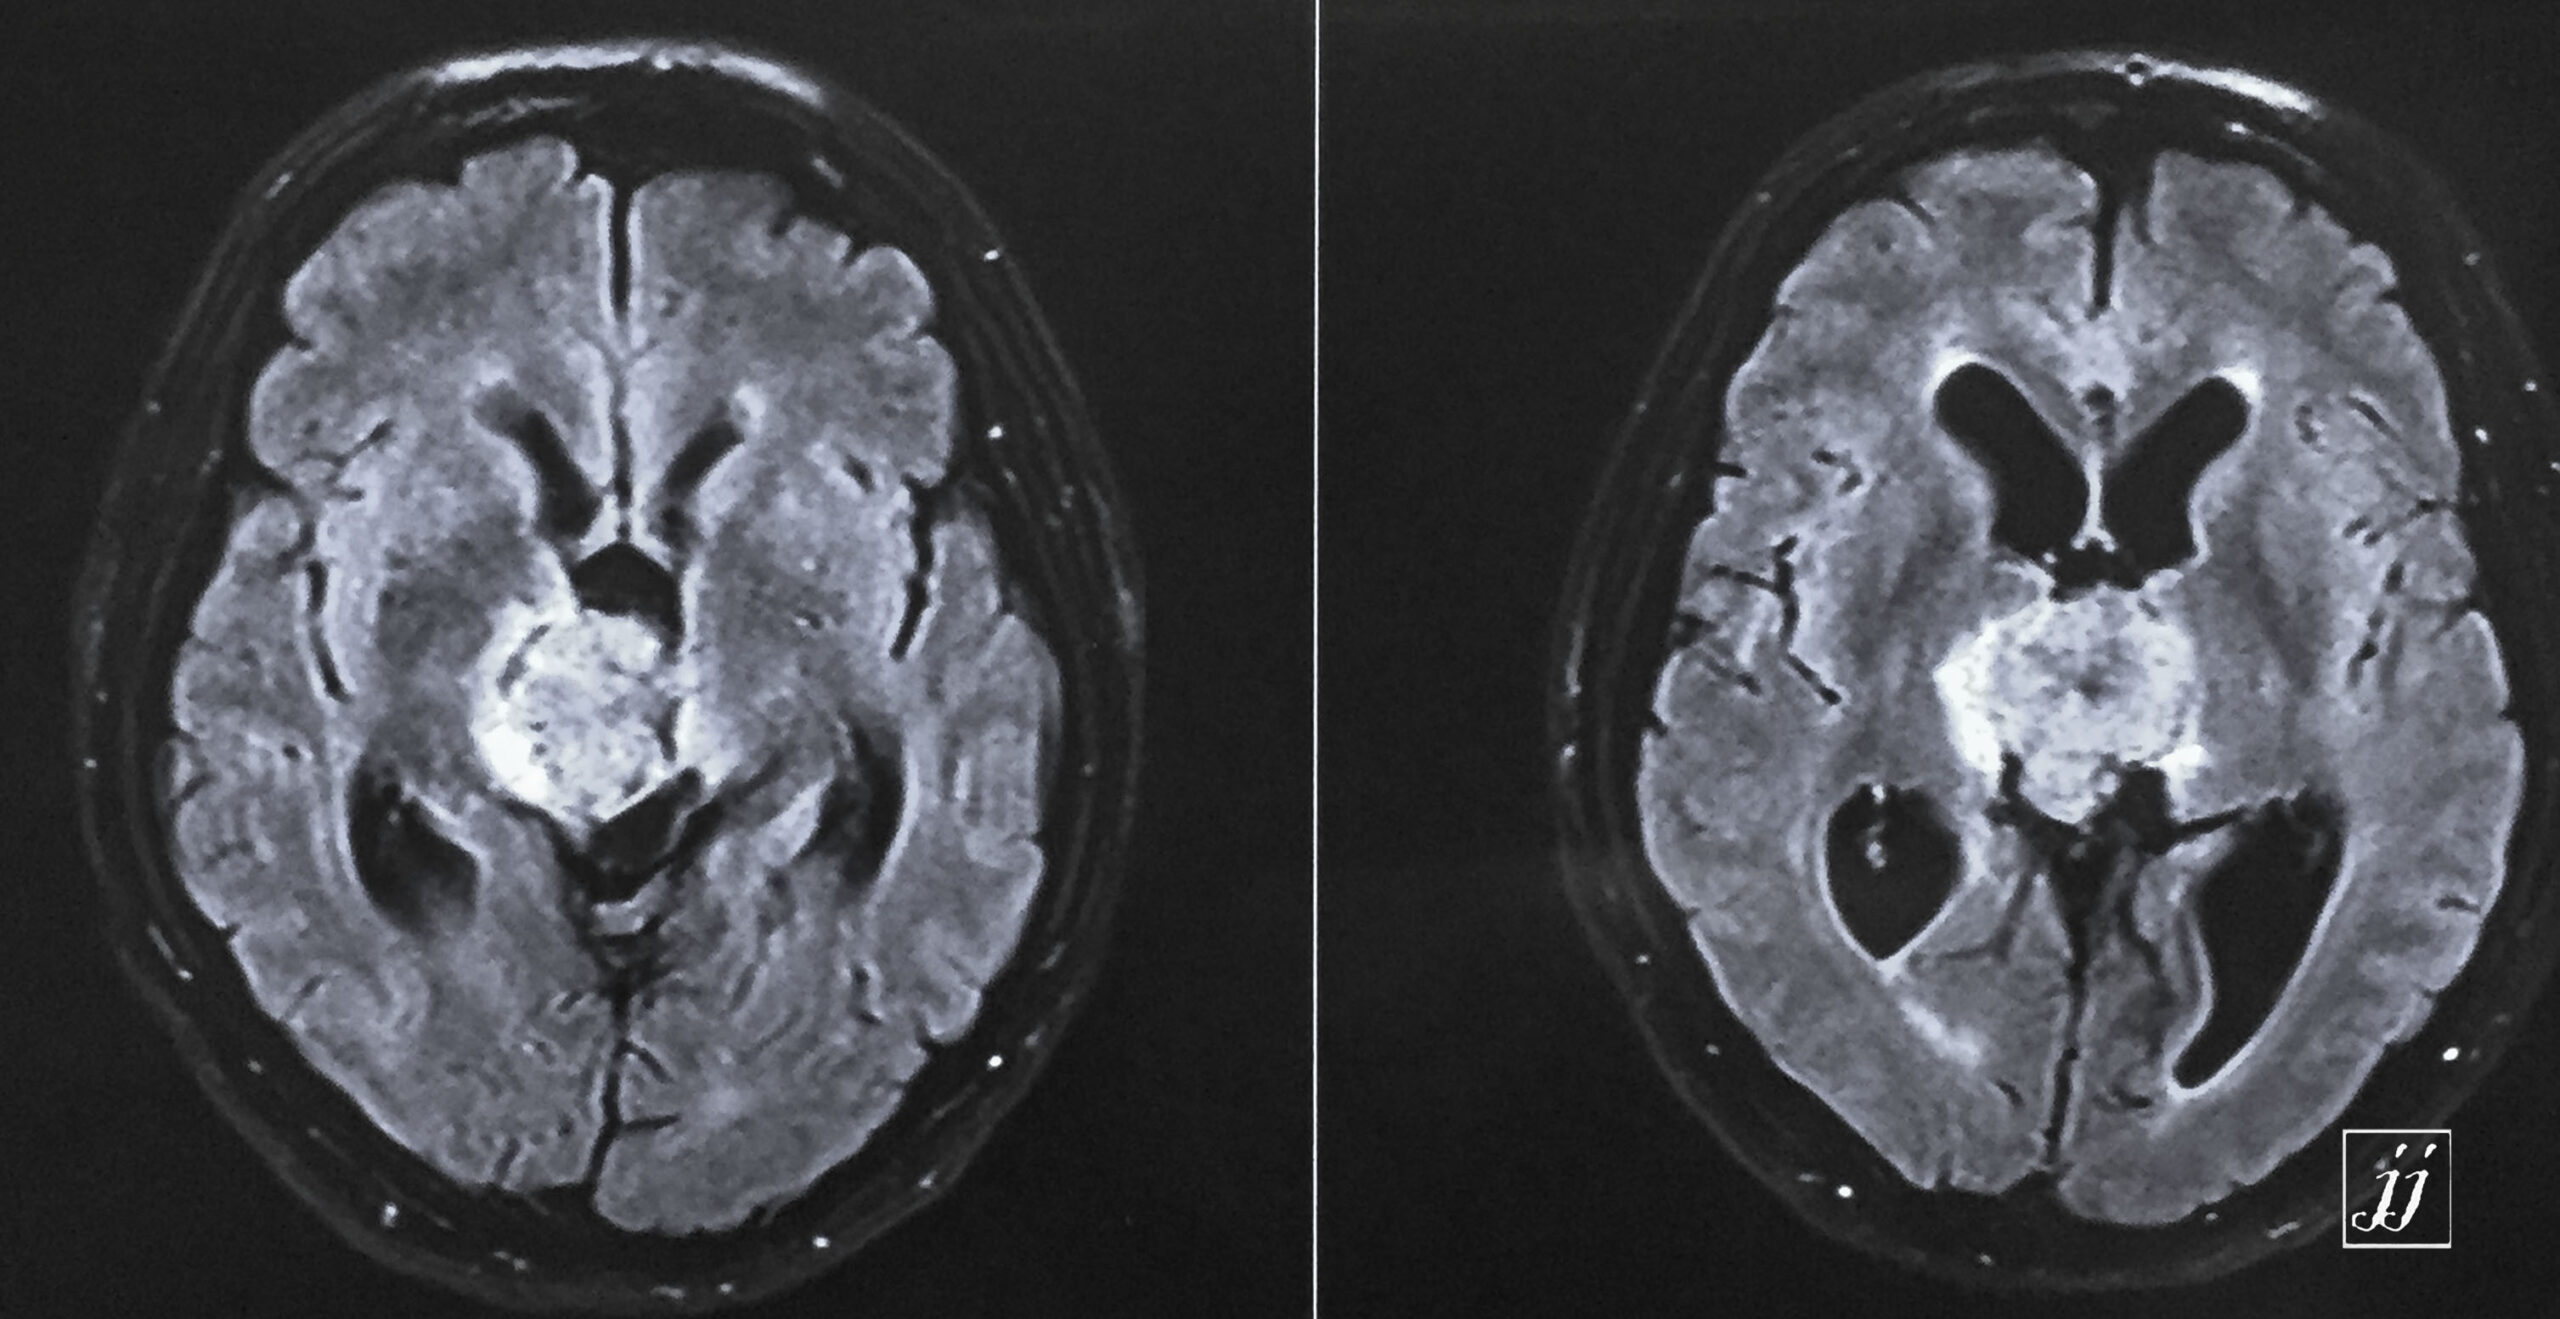

Brain- hugged size tectal and quadrigeminal meningioma (10)